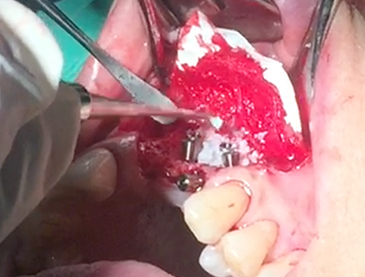

Simultaenous bone grafting for implants

Implants/Bone Grafting

Partial edentulous clinical cases